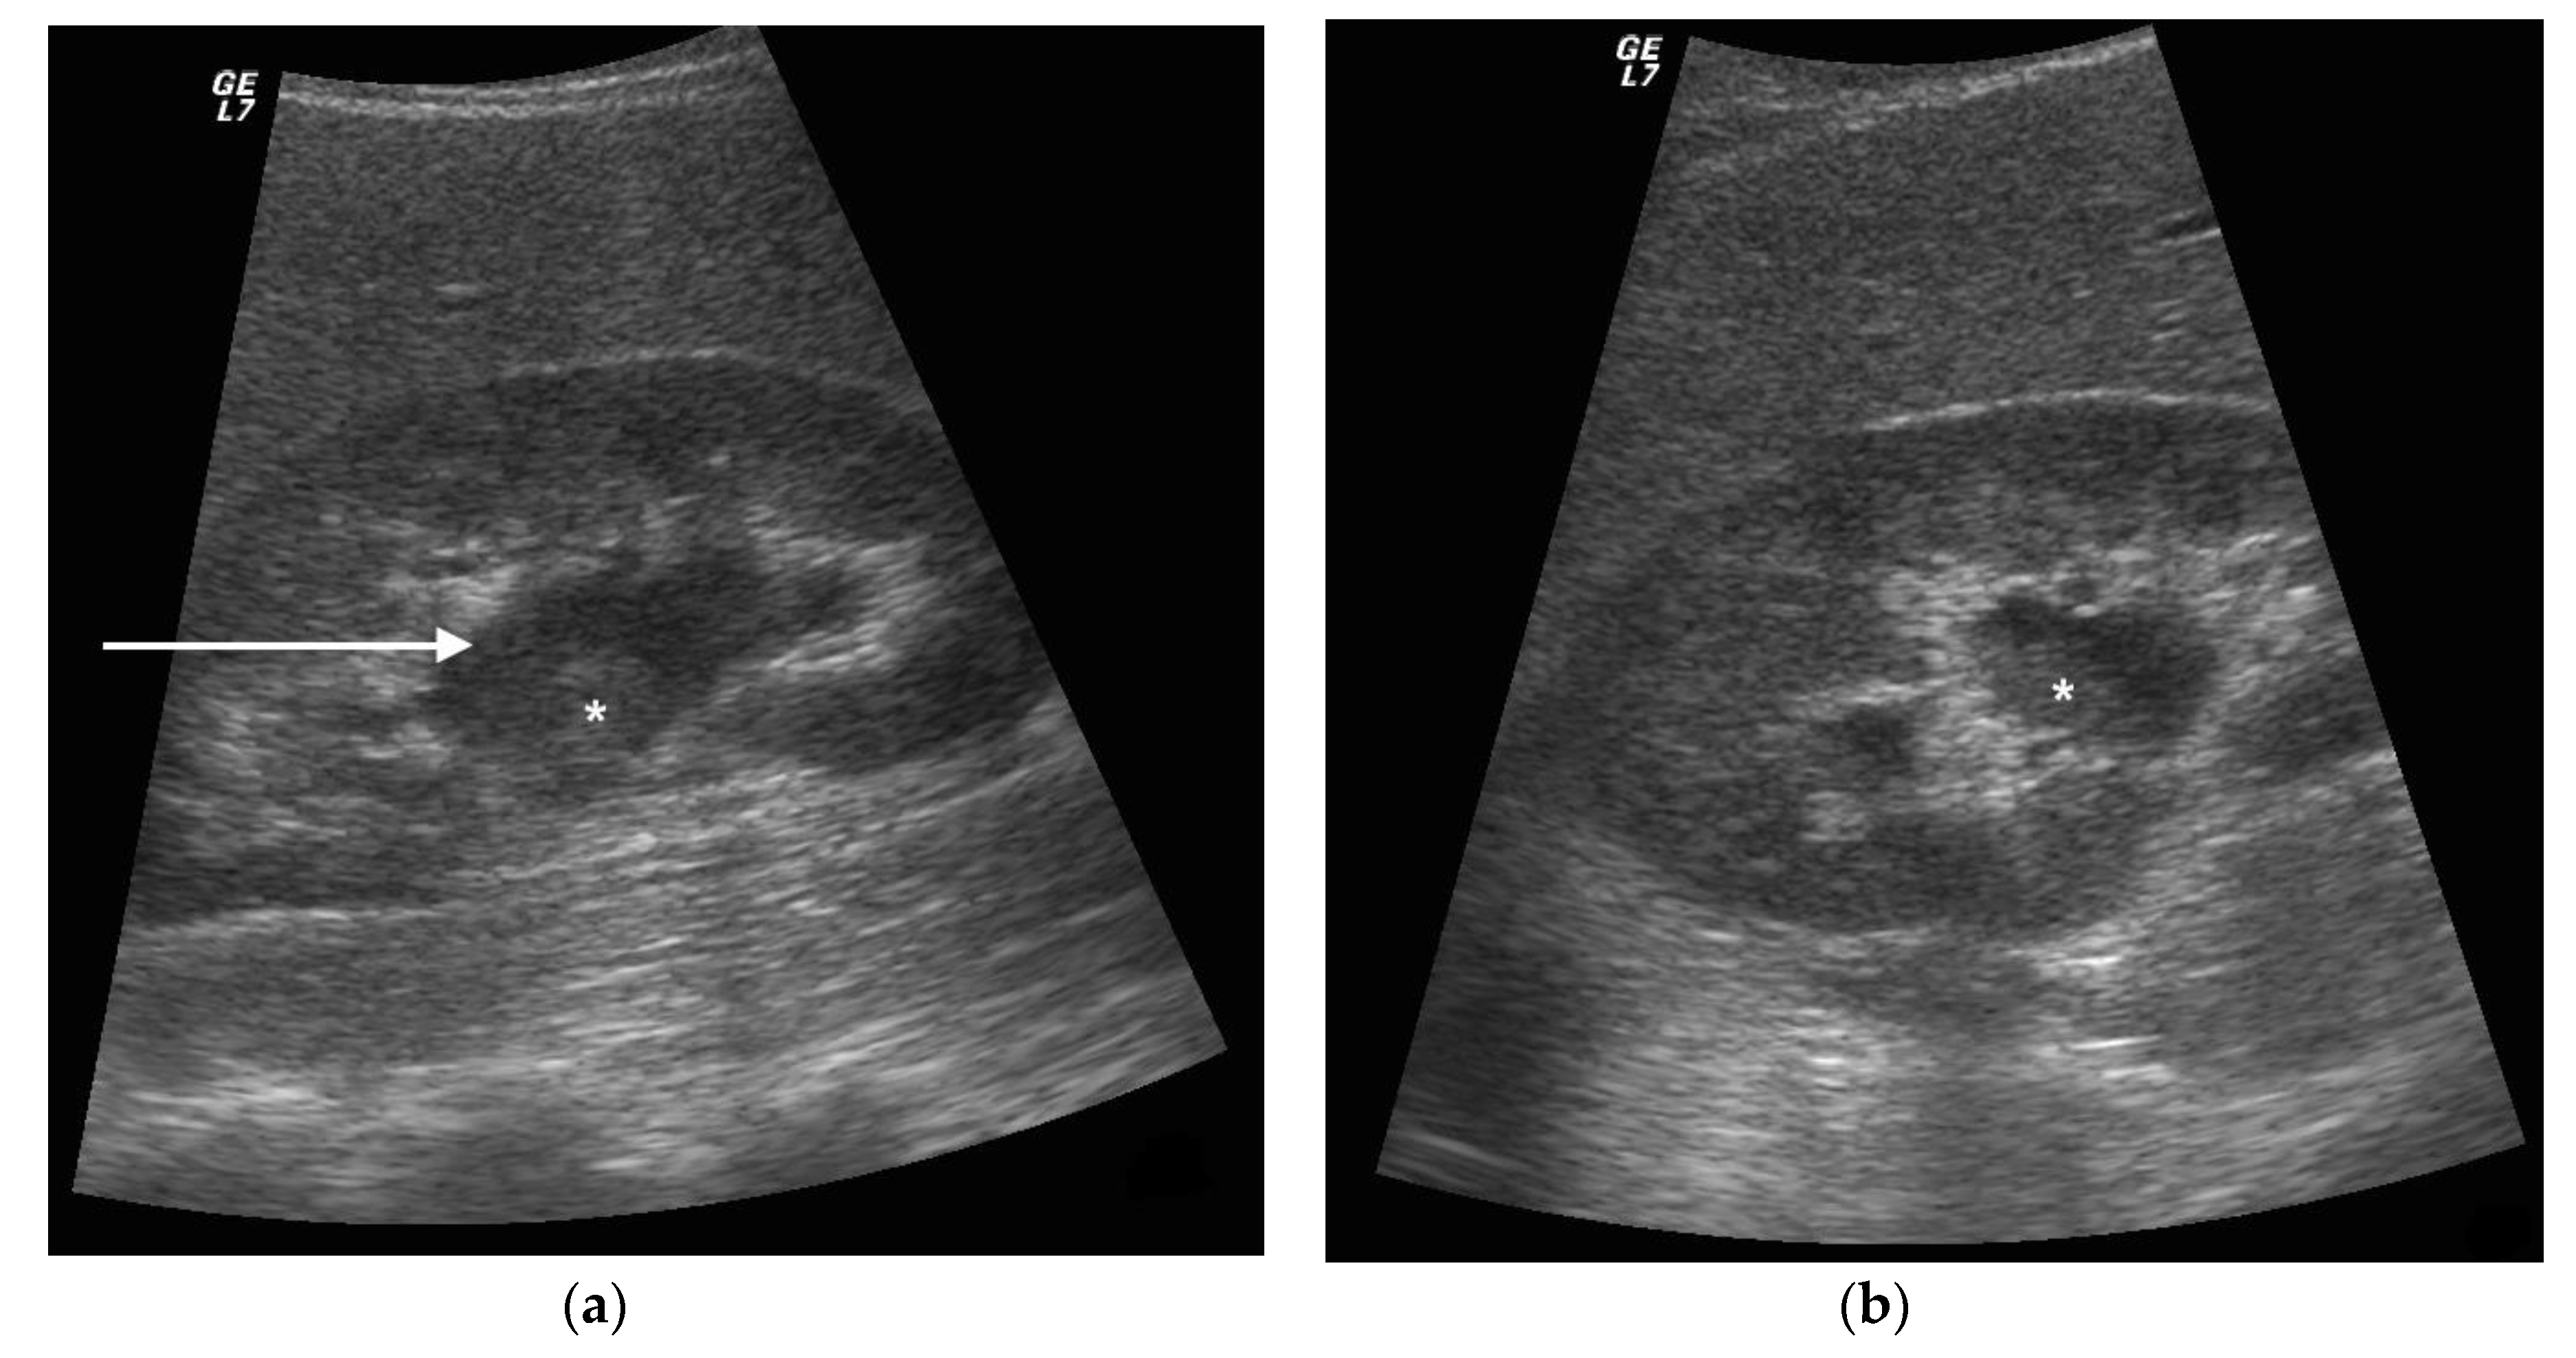

3. Ultrasound

4. CT